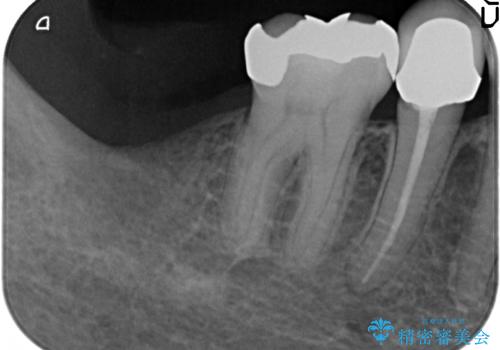

- 右下7番にインプラント治療を行った症例です。

CT撮影を行い状態を確認後、インプラント(ストローマン)の埋入(一次手術)を行いました。

インプラントと骨の定着を待った後に二次手術を行い、カスタムアバットメント、オールセラミッククラウンによる補綴を行いました。